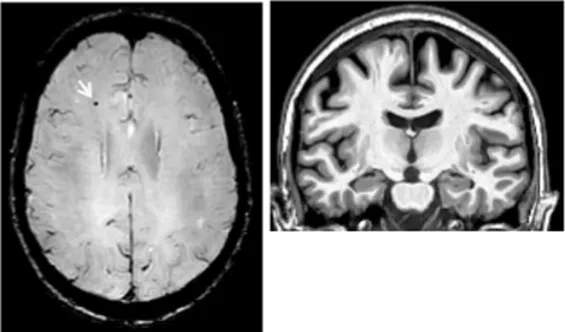

On an individual level, we observed a complex dissociation as the neuroinflammatory PET profiles appeared not to be predictive of patients’ clinical profiles and vice versa (Table 2): some patients with similar clinical presentations had opposed patterns of neuroinflammation, while other patients with opposite clinical presentations showed similar patterns of neuroinflammation.

Table 2

| Clinical findings | CSF and APOE | SWI and T1-weighted MRI scans | Proposition of ongoing neuroinflammatory processes |

|---|---|---|---|

| Case 5: a 64 y.o. man who was referred for a memory complaint. At screening, he had 24/30 MMSE and impairment on episodic memory, denomination and categorical verbal fluency tests. On MRI, multiple lobar microbleeds without hemisiderosis were observed as well as WMH (Fazekas’s score of 8/9) and moderate cortical atrophy. | Aβ42: 208 P-tau: 184 T-tau: 1449 APOE E3/E3 TSPO MAB | ![]() | ![]() Toxic neuroinflammation associated with mixed angiopathy and AD pathological progression. |

| Case 21: a 59 y.o. woman with early onset symptoms and familial history of AD. At screening, she had 23/30 MMSE and impairment on episodic memory, executive functions, processing speed and categorical verbal fluency tests. Three lobar microbleeds, WMH (Fazekas’s score of 3/9) and moderate cortical atrophy were observed on MRI. | Aβ42: 462 P-tau: 140 T-tau: 768 APOE E3/E4 TSPO MAB | ![]() | ![]() Low cortical neuroinflammation compared to the cerebellar cortex. |

| Case 2: a 66 y.o. woman with familial history of AD who was referred for a memory complaint. At screening, she had 30/30 MMSE, preserved memory, executive functions and processing speed but encoding impairment in visual recognition memory as well as decreased scores on long-term forgetting tests. Two lobar and one deep microbleed without hemosiderosis, WMH (Fazekas’s score of 5/9) and moderate cortical atrophy were observed on MRI. | Aβ42: 327 P-tau: 79 T-tau: 479 APOE E2/E4 TSPO HAB | ![]() | ![]() Protective neuroinflammation that might be compensatory to the amyloid load in the frontal and cingulate regions in the absence of spread tau pathology and neurodegeneration. |

| Case 12: a 64 y.o. man with early onset atypical AD in a posterior cortical atrophy variant. He presented a familial history of AD. At screening, he had 21/30 MMS, multi-domain cognitive impairment, especially constructive apraxia and visual apperceptive agnosia. WMH (Fazekas’s score of 5/9) and cortical atrophy were observed on MRI. | Aβ42: 481 P-tau: 103 T-tau: 669 APOE E3/E3 TSPO HAB | ![]() | ![]() Toxic neuroinflammation associated with AD pathological progression, especially in posterior cortical regions. |

Dissociation between clinical and neuroinflammatory PET profiles in early AD.

All fourth patients are right-handed. TSPO PET imaging showed SUVR relative to the cerebellar cortex and is represented in standard space in the same slice and intensity scale, whereas MRI scans are shown in native space. Cerebrospinal fluid AD biomarker values were abnormal for the four patients (see the method section for details).

Aβ42, amyloid-β 42; AD, Alzheimer’s disease; APOE, apolipoprotein E; CAA, cerebral amyloid angiopathy; CSF, cerebrospinal fluid; MMS, mini-mental state examination; MRI, magnetic resonance imaging, P-tau, phosphorylated tau; SWI, susceptibility-weighted imaging; T-tau, total-tau; TSPO, translocator protein; WB, whole brain; WMH, white matter hyperintensities.